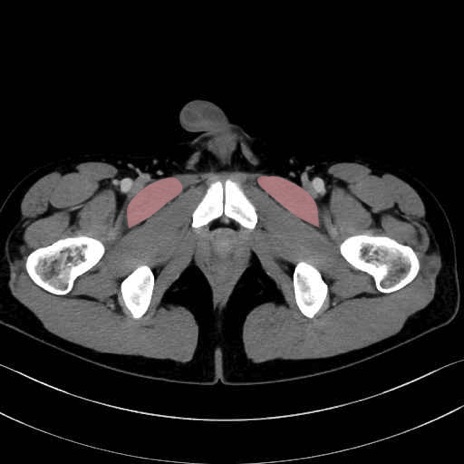

恥骨筋 (Pectineus)